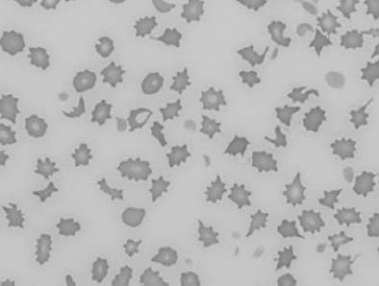

Figure 1.10 Canine blood film showing echinocytes I (also see color section).

Figure 1.11 Canine blood film showing echinocytes III (also see color section).